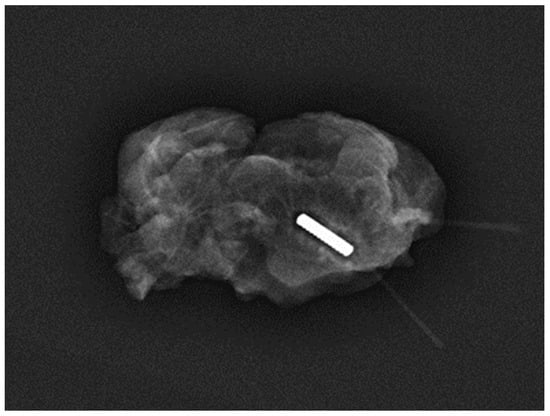

Magseed® technology, introduced into clinical practice in 2016, has undergone improvements to enhance user-friendliness and MRI compatibility, expanding its utility []. Initially utilised primarily for non-palpable breast lesions [], its acceptance for axillary applications has gradually increased. However, there remains limited literature on its efficacy in aiding TAD. Our analysis, encompassing 494 Magseed® TAD procedures, provides evidence of its performance since the publication of the first study by Greenwood et al. in 2019. The 100% successful deployment rate is facilitated by the small size of the seed (5 × 1 mm) and narrow bore of the introducer needle (18 gauge) [] (Figure 3).

Figure 3.

Specimen radiograph of a magnetic seed containing a lymph node harvested during TAD in a 65-year-old patient who received NST after the deployment of the seed (Magseed®).